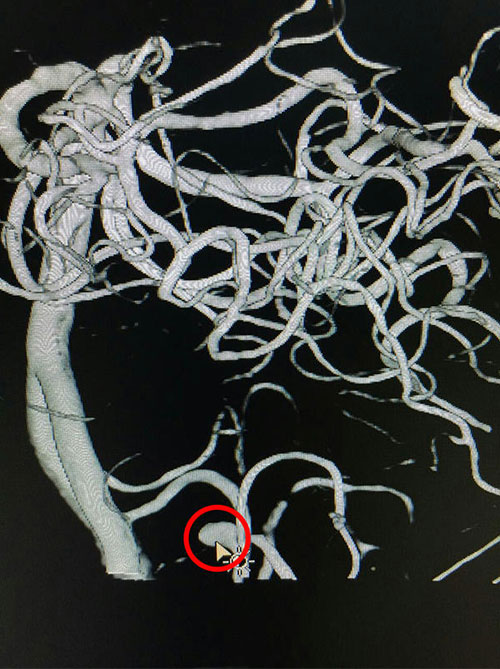

術(shù)前血管造影,紅圈內(nèi)箭頭指向處動脈瘤瘤體

為求進(jìn)一步治療,11月22日許先生來到我院就診,患者訴左側(cè)肢體乏力、麻木伴吐詞不清。我院神外科專家潘仁龍主任仔細(xì)診查經(jīng)后,認(rèn)為患者先前腦出血診斷不明確,考慮顱腦內(nèi)可能有其他問題,遂建議行全腦血管造影術(shù)檢查及完善其他相關(guān)檢查。11月24日DSA造影結(jié)果提示:“左小腦后下動脈瘤”,初步診斷為:1.腦干出血后遺癥期;2.高血壓病III級,極高危組;3.右側(cè)面神經(jīng)癱瘓。補(bǔ)充診斷:左小腦后下動脈動脈瘤”。